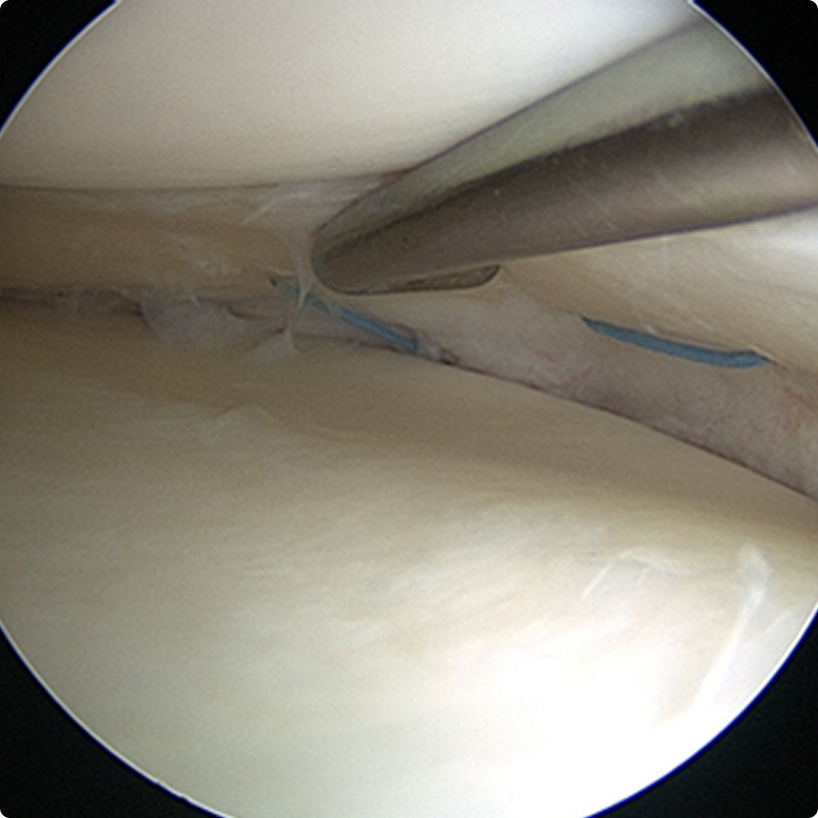

Günümüzde ön çapraz bağ onarımı ameliyatı artroskopik (kapalı) yöntemle yapılmaktadır. Uygun kalınlık ve uzunlukta alınan bağ diz eklemini oluşturan iki kemiğin içinde açılan tünellerden geçirilerek kemiklere çeşitli metal ve metal olmayan materyallerle tespit edilir.